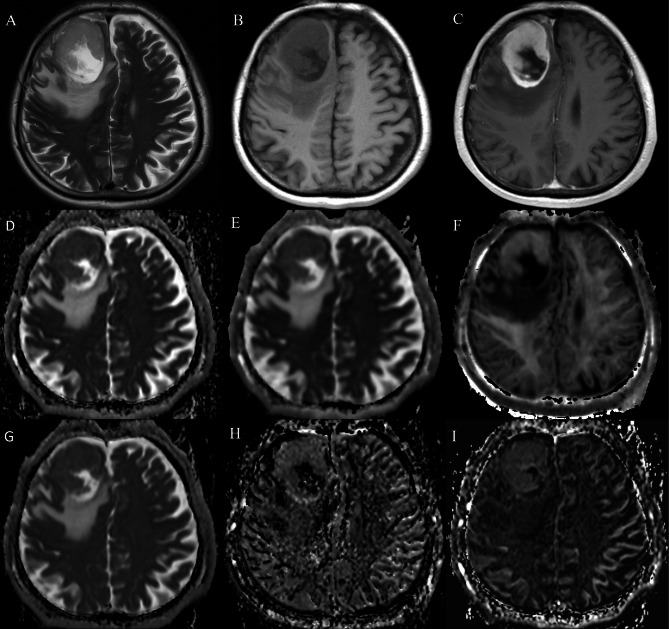

Methods and materials: A total of 422 participants who had DWI, DKI, and IVIM were enrolled between January 2020 and March 2024. The histogram characteristics of ADC, diffusional kurtosis(K), diffusion coefficient (Dk), pseudo-diffusion coefficient(D*), pure diffusion coefficient(D), perfusion fraction(f) in the solid component of tumors were calculated. Groups were compared by IDH genotype and 1p/19q codeletion status, utilizing logistic regression analysis and receiver operating characteristic curve to evaluate the differential diagnostic performance in predicting IDH and 1p/19q genotypes.

Results: Significant differences were observed in thirty-nine histogram-based features of diffusion parameters between IDH mutant gliomas and IDH wildtype glioblastoma. In IDH mutant gliomas, significant differences were found in thirty-six histogram-based features of DWI, DKI and IVIM parameters between those with and without 1p/19q codeletion. The IVIM model and the combined model showed superior diagnostic performance compared to the DWI model in terms of AUCs for predicting IDH mutations (0.903, 0.913 and 0.807, respectively p < 0.05), and 1p/19q codeletion in IDH mutant gliomas (0.825, 0.855, and 0.769, respectively; p < 0.05). Correlations between Ki-67 and the mean values of ADC, Dk, K, D, D*, and f were significant, with correlation coefficients from - 0.17 to 0.36 (all p < 0.05).